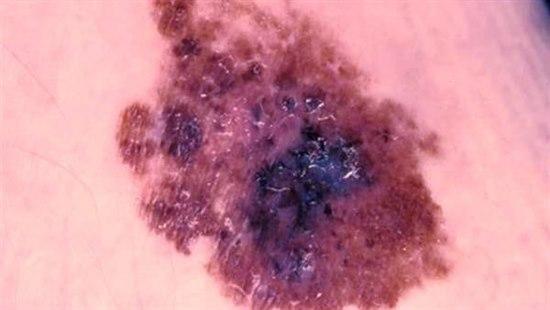

Malingt melanom er en ondartet svulst i huden utgått fra melanocytter i basallaget i epidermis. Den kan også utgå fra melanocytter i slimhinner eller øye. Malingt melanom er den kreftformen som har økt mest i løpet av de siste 50 år. I Norge er det registrert rundt en ti-dobling i insidens. Hvite mennesker har 10 ganger høyere risiko enn mørkhudete.